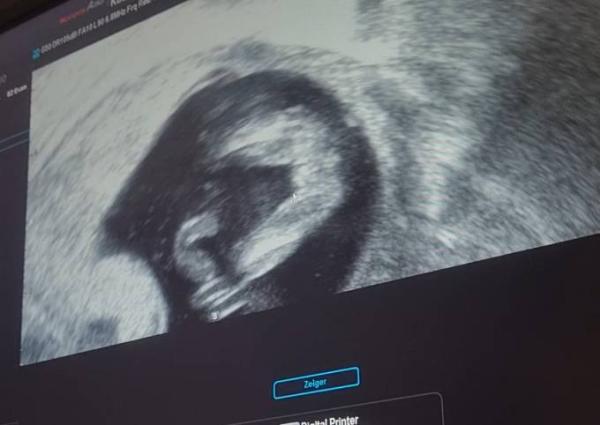

Und hier noch ein Schnappschuss:)

Bild zu